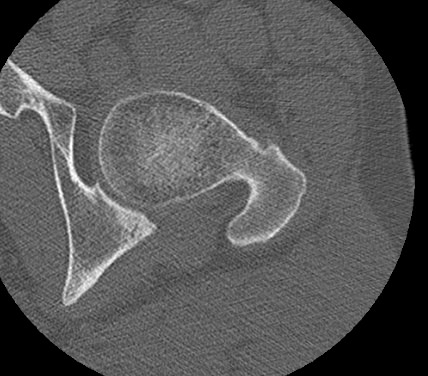

КТ относится к лучевым методам исследования, то есть предусматривает использование рентгеновского излучения, которое хорошо поглощается костной тканью. В результате сканирования и последующей цифровой обработки полученных данных получаются подробные снимки в различных плоскостях, а также трехмерные изображения тазобедренных суставов, позволяющие оценить пространственное расположение суставных поверхностей, внутрисуставных структур и окружающих тканей.

Снимки высокого разрешения позволяют выявить минимальные изменения в костных структурах и окружающих тканях. Мультиспиральная КТ может применяться в экстренных ситуациях для диагностики травматических повреждений тазобедренных суставов, в частности, при переломах шейки бедра. Кроме того, исследование незаменимо при планировании оперативного вмешательства, а также в послеоперационном периоде для оценки успешности проведенной операции и для отслеживания процесса восстановления.

Что показывает КТ тазобедренного сустава

- повреждения костной ткани (перелом головки, шейки бедра, вертлужной впадины);

- вывих и подвывих;